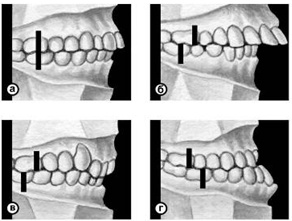

Рис. 6. Схематическое изображение челюстей при сагиттальных аномалиях прикуса, по классификации Энгла: а — аномалии первого класса; б — аномалии второго класса, первого подкласса; в — аномалии второго класса, второго подкласса; г — аномалии третьего класса; вертикальными линиями указано соотношение верхнего и нижнего первых моляров.